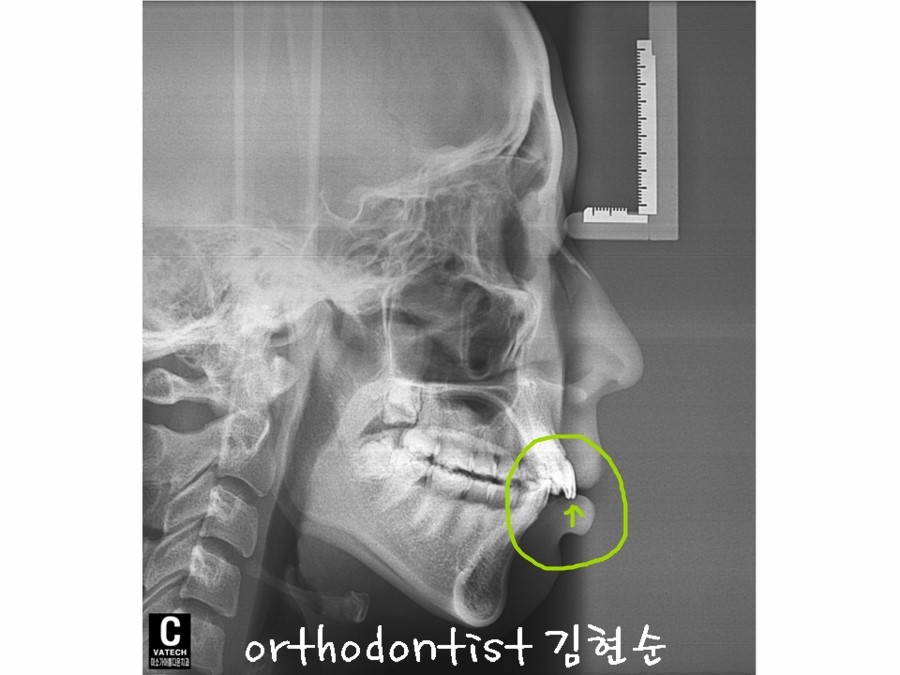

치료 계획은 발치 교정입니다만, 아래는 뽑지 않고, 위 치아만 양측으로 두개 발치하면서 교정하기로 하였습니다. .

치료 계획은 발치 교정입니다만,

아래는 뽑지 않고,

위 치아만 양측으로 두개 발치하면서

교정하기로 하였습니다.